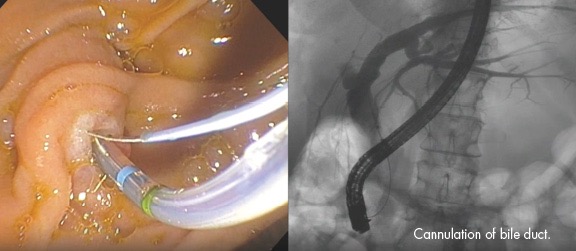

1. 내시경적 역행성 담췌관조영술(ERCP)

- 총담관 담석은 심각한 합병증을 동반할 수 있으므로 증상이 없는 총담관 담석이라도 제거를 해야 한다.

- 담석 혹은 담도염의 증거가 있는 경우에 시행한다. 뚜렷한 증거 없이 진단적 목적으로 시행하지 않는다.